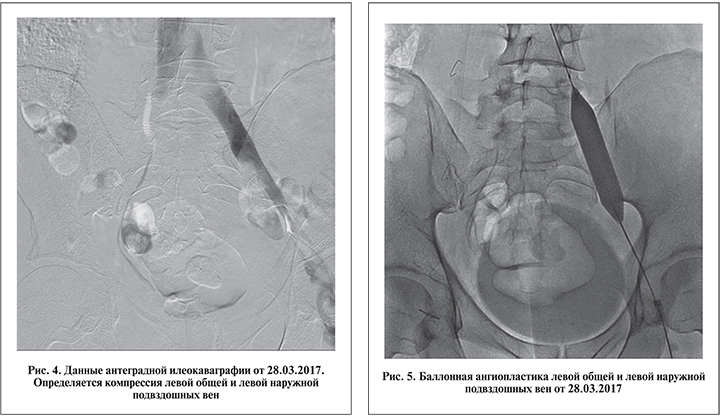

Интраоперационная дистально восходящая флебография выявила сочетанную артериовенозную компрессию: между правой общей подвздошной артерией и левой общей подвздошной веной (синдром Мея–Тюрнера), между левой наружной подвздошной артерией и левой наружной подвздошной веной (рис. 4).

Поскольку фиброзные внутрипросветные спайки (шварты) в компрессированной подвздошной вене встречаются в большинстве случаев, будучи неизбежным патогенетическим звеном этого заболевания, проведение ангиопластики перед стентированием мы считали обязательным этапом операции (рис. 5).